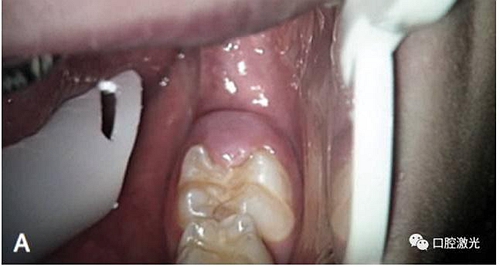

激光盲袋切除術(shù)前

術(shù)中